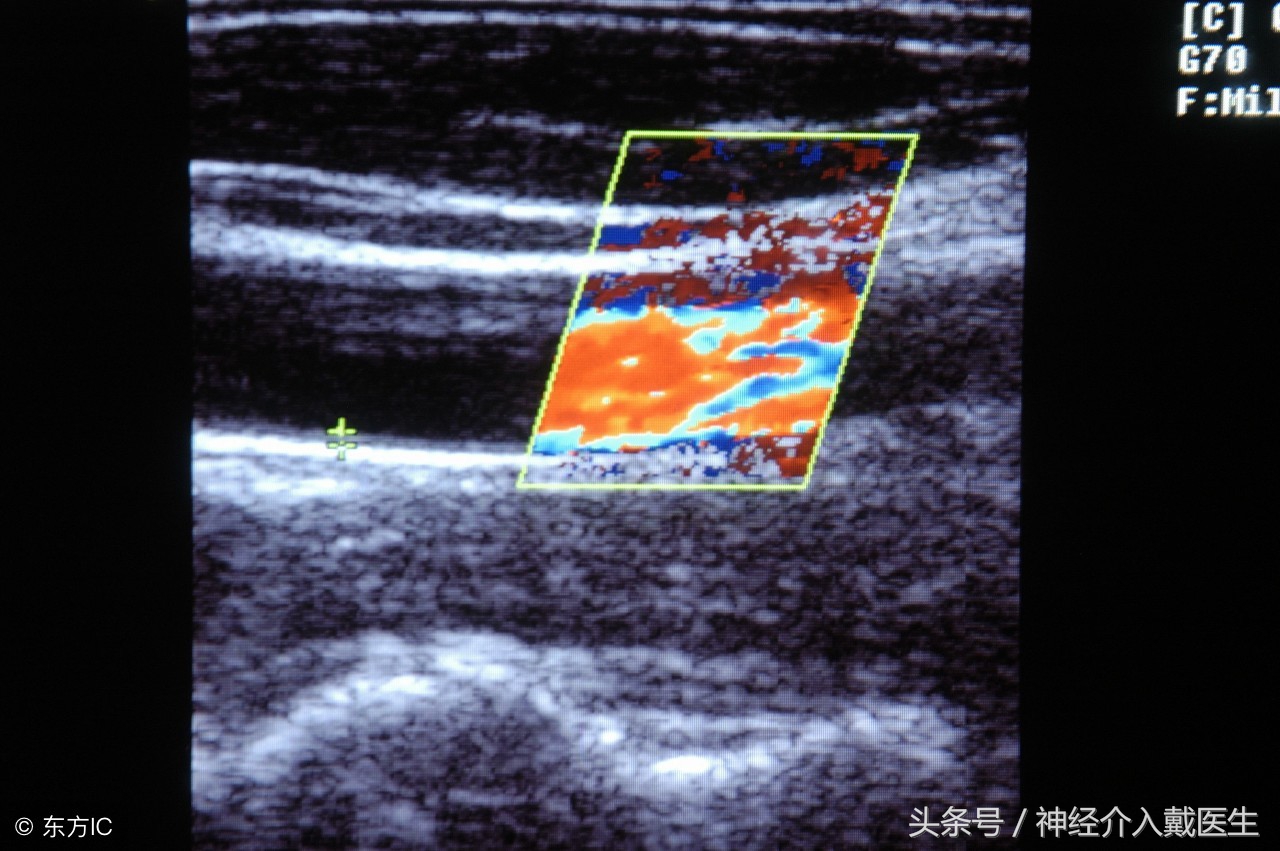

颈动脉彩超是目前首选的无创性颈动脉检查手段,具有简便、安全和费用低廉的特点。它不仅可显示颈动脉的解剖图像,进行斑块形态学检查,如区分斑块内出血和斑块溃疡,而且还可显示动脉血流量、流速、血流方向及动脉内血栓。诊断颈动脉狭窄的准确性在95%以上,多普勒-彩色超声检查已被广泛地应用于颈动脉狭窄病变的筛选和随访中。在动脉粥样硬化的流行病学调查和对动脉粥样硬化预防、治疗试验的有效性评价中起着关键作用。

动脉彩超检查通过超声影像技术,通过超声波反射的原理,评估颈部血管正常解剖结构、血管走行和血流信息,清晰显示血管有无内中膜增厚、有无斑块形成、斑块形成的部位、大小,评估是否有无血管狭窄及狭窄程度、有无闭塞。来判断血管疾病如高血压病、糖尿病、冠心病、脑卒中等风险。 近年来的研究提示颈动脉内中膜厚度与心肌梗塞的发生有着明显的相关性;内中膜厚度每增加0.1mm,心肌梗塞发生的危险性上升11%。高危人群最好筛查颈动脉彩超,以便尽早发现颈动脉斑块,了解斑块的大小和性质,并及时调整饮食或药物,控制斑块发展。 像我们脑血管疾病筛查通常是做颈动脉彩超。既经济,有能够发现许多问题。